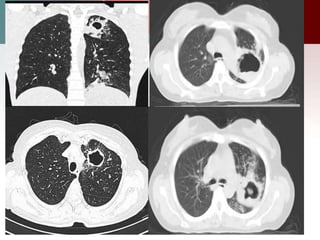

CCAM type I

CT scan shows multiple large cysts (>2cm) involving the lower lobe of left lung. The cysts

are air-filled, expand the lower lobe, cause mediastinal shift and hypoplasia of right lung